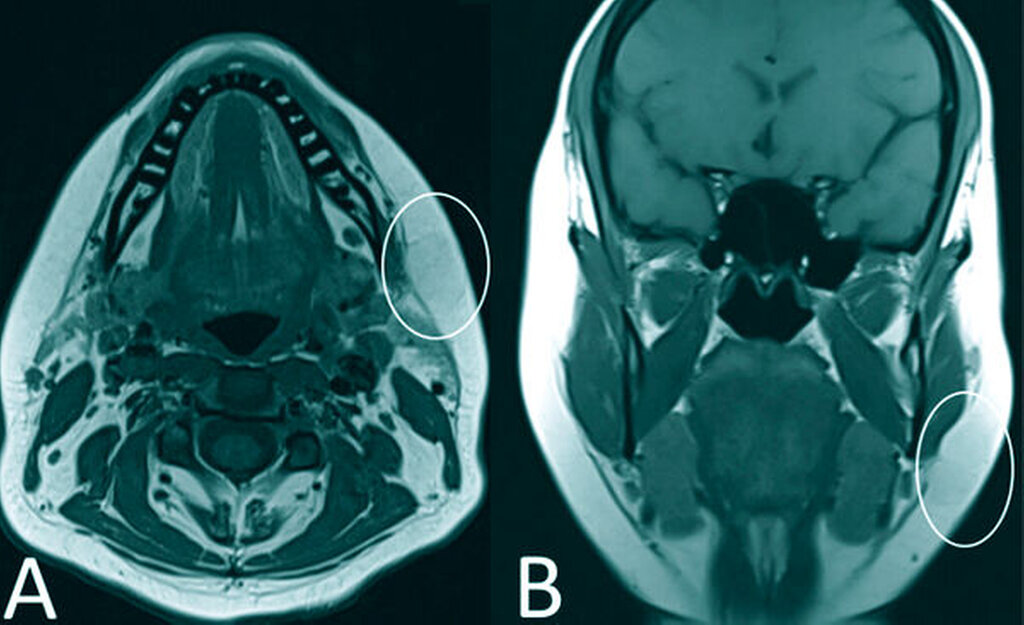

Palpatorisch präsentierte sich ein prall-kugeliger Tumor, der zum umliegenden Gewebe gut verschieblich war. Die bildgebende Diagnostik mittels B-Mode-Sonografie zeigte eine echoreiche, scharf begrenzte Raumforderung mit dorsaler Schallverstärkung (Abbildung 2). Aus der Zusammenschau aus klinischem und sonografischem Bild wurde der Verdacht auf ein Lipom gestellt. Die alio loco angefertigte MRT bekräftigte diese Verdachtsdiagnose, zudem zeigte sich darin die Unterbrechung des Platysma durch das verdrängende Wachstum des Befunds in die Tiefe (Abbildung 3).